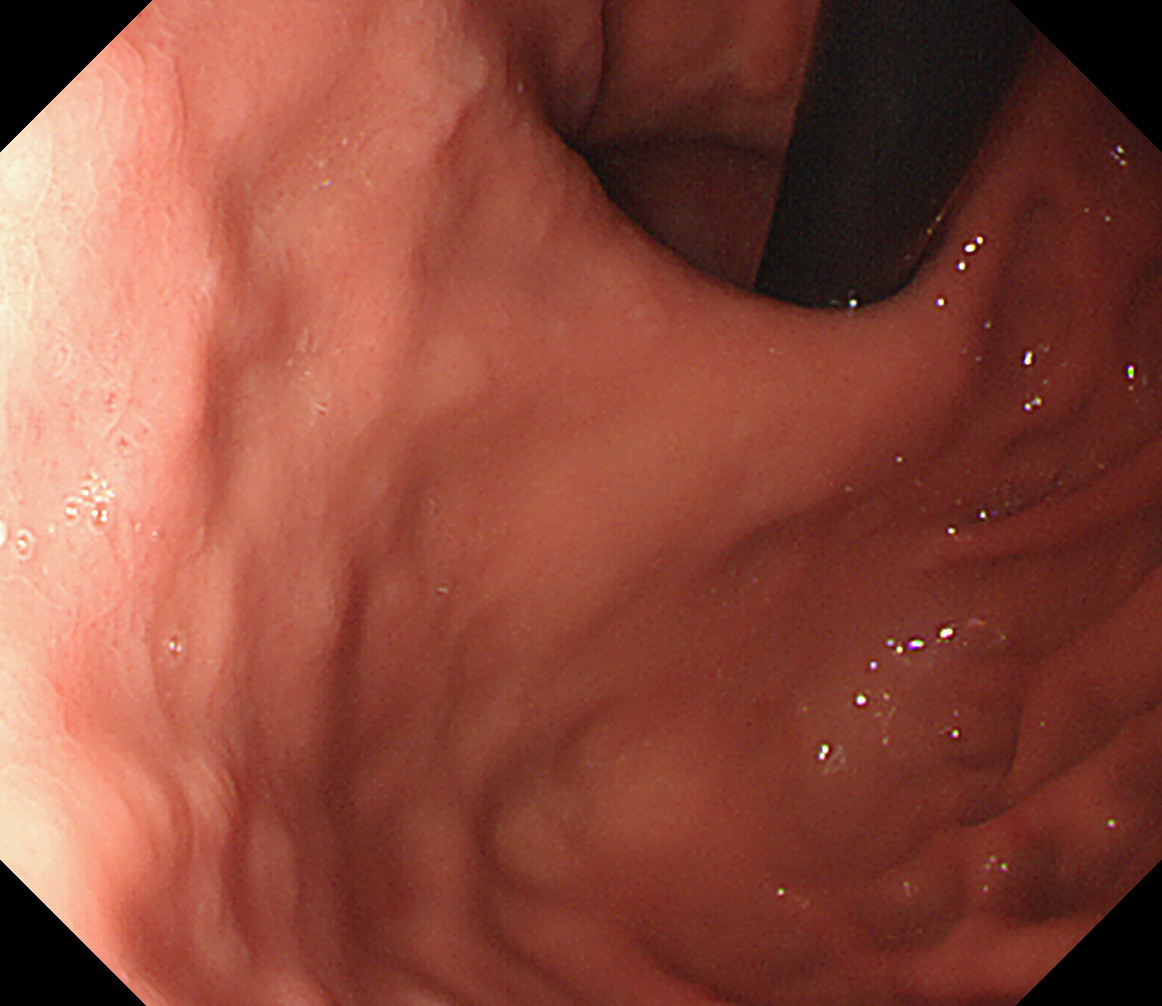

11 胃角部後壁 [見下ろし]になります 中部食道

12 胃角部小弯 [J反転]見上げになります 胃角部後壁

13 胃角部前壁 再度、[見下ろし]になります 胃角部前壁